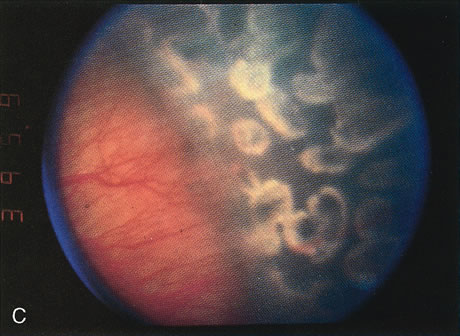

The indications for scleral buckling surgery are stage 4A with progression, stage 4B or open funnel stage 5 retinal detachment. Stage 4A retinal detachment (Fig. 7A) is subtotal, and spares the fovea. The CryoROP study demonstrated resolution in 46.1% of eyes with stage 4A retinal detachments at 4½ years. 61 Unfortunately, the study also showed a 17.9% risk of progression for stage 4A eyes to total retinal detachment. Stage 4B retinal detachment (Fig. 7B), which is due to progressive exudation or traction, involves detachment of the fovea. Stage 5 retinal detachment (Fig. 7C) is total; it may have an open or closed funnel configuration. When the detachment is funnel shaped, the funnel is divided into anterior and posterior parts, and may be open or closed in either location.

Fig. 7. A. Stage 4A ROP. Subtotal retinal detachment does not involve the fovea. B. Stage 4B ROP. Subtotal retinal detachment involves the fovea. C. Stage 5 ROP. Total retinal detachment. The detachment may be shallow, with an open funnel configuration, as in this example. Note the loss of the choroidal vascular pattern because of subretinal fluid.